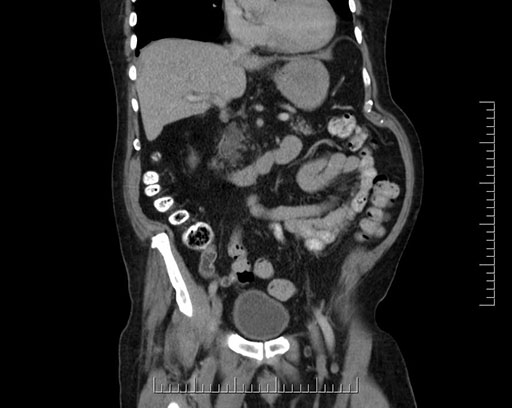

Whipple (pancreaticoduodenectomy) [case 7]

Look through the patient's CT scan to identify any areas of concern for the necessary procedure.

Imaging analysis

Based on your CT findings, which issue(s) would give reason for "planned slowing down moment(s)" in this case?

Considering a standard Whipple procedure, what step(s) of the operation would you do differently in this case?